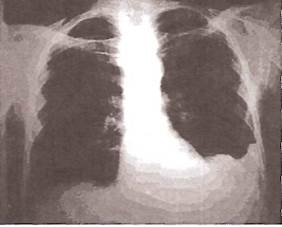

По мере нарастания объема экссудата на рентгенограммах начинает определяться однородное затемнение, которое прилежит к наружному краю грудной клетки и диафрагме. Верхняя граница затемнения чаще располагается косо — сверху вниз и снаружи кнутри (рис. 23). При перемене положения тела затемнение и его верхняя граница меняют свою форму и расположение в связи с перемещением жидкости (рис. 24).

При скоплении в плевральной полости большого количества экссудата в нижнебоковых отделах легочного поля появляется значительных размеров треугольная тень с косой верхней внутренней границей. При этом купол диафрагмы уплощается, а средостение смещается в здоровую сторону (рис. 25).

Рис. 23. Рентгенограмма легких при экссудативном плеврите и умеренном количестве плевральной жидкости.

Заметно интенсивное затемнение нижнего легочного поля слева, небольшое увеличение левой половины грудной клетки. Смещение средостения отсутствует

Рис. 25. Рентгенограмма легких больного с правосторонним экссудативным плевритом

Выявлению малых количеств плеврального выпота (более 100-150 мл) помогает латерография — рентгенологическое исследование в положении пациента на боку на стороне поражения (рис. 26). При наличии свободной неосумкованной жидкости появляется пристеночная узкая лентовидная тень (рис. 27).